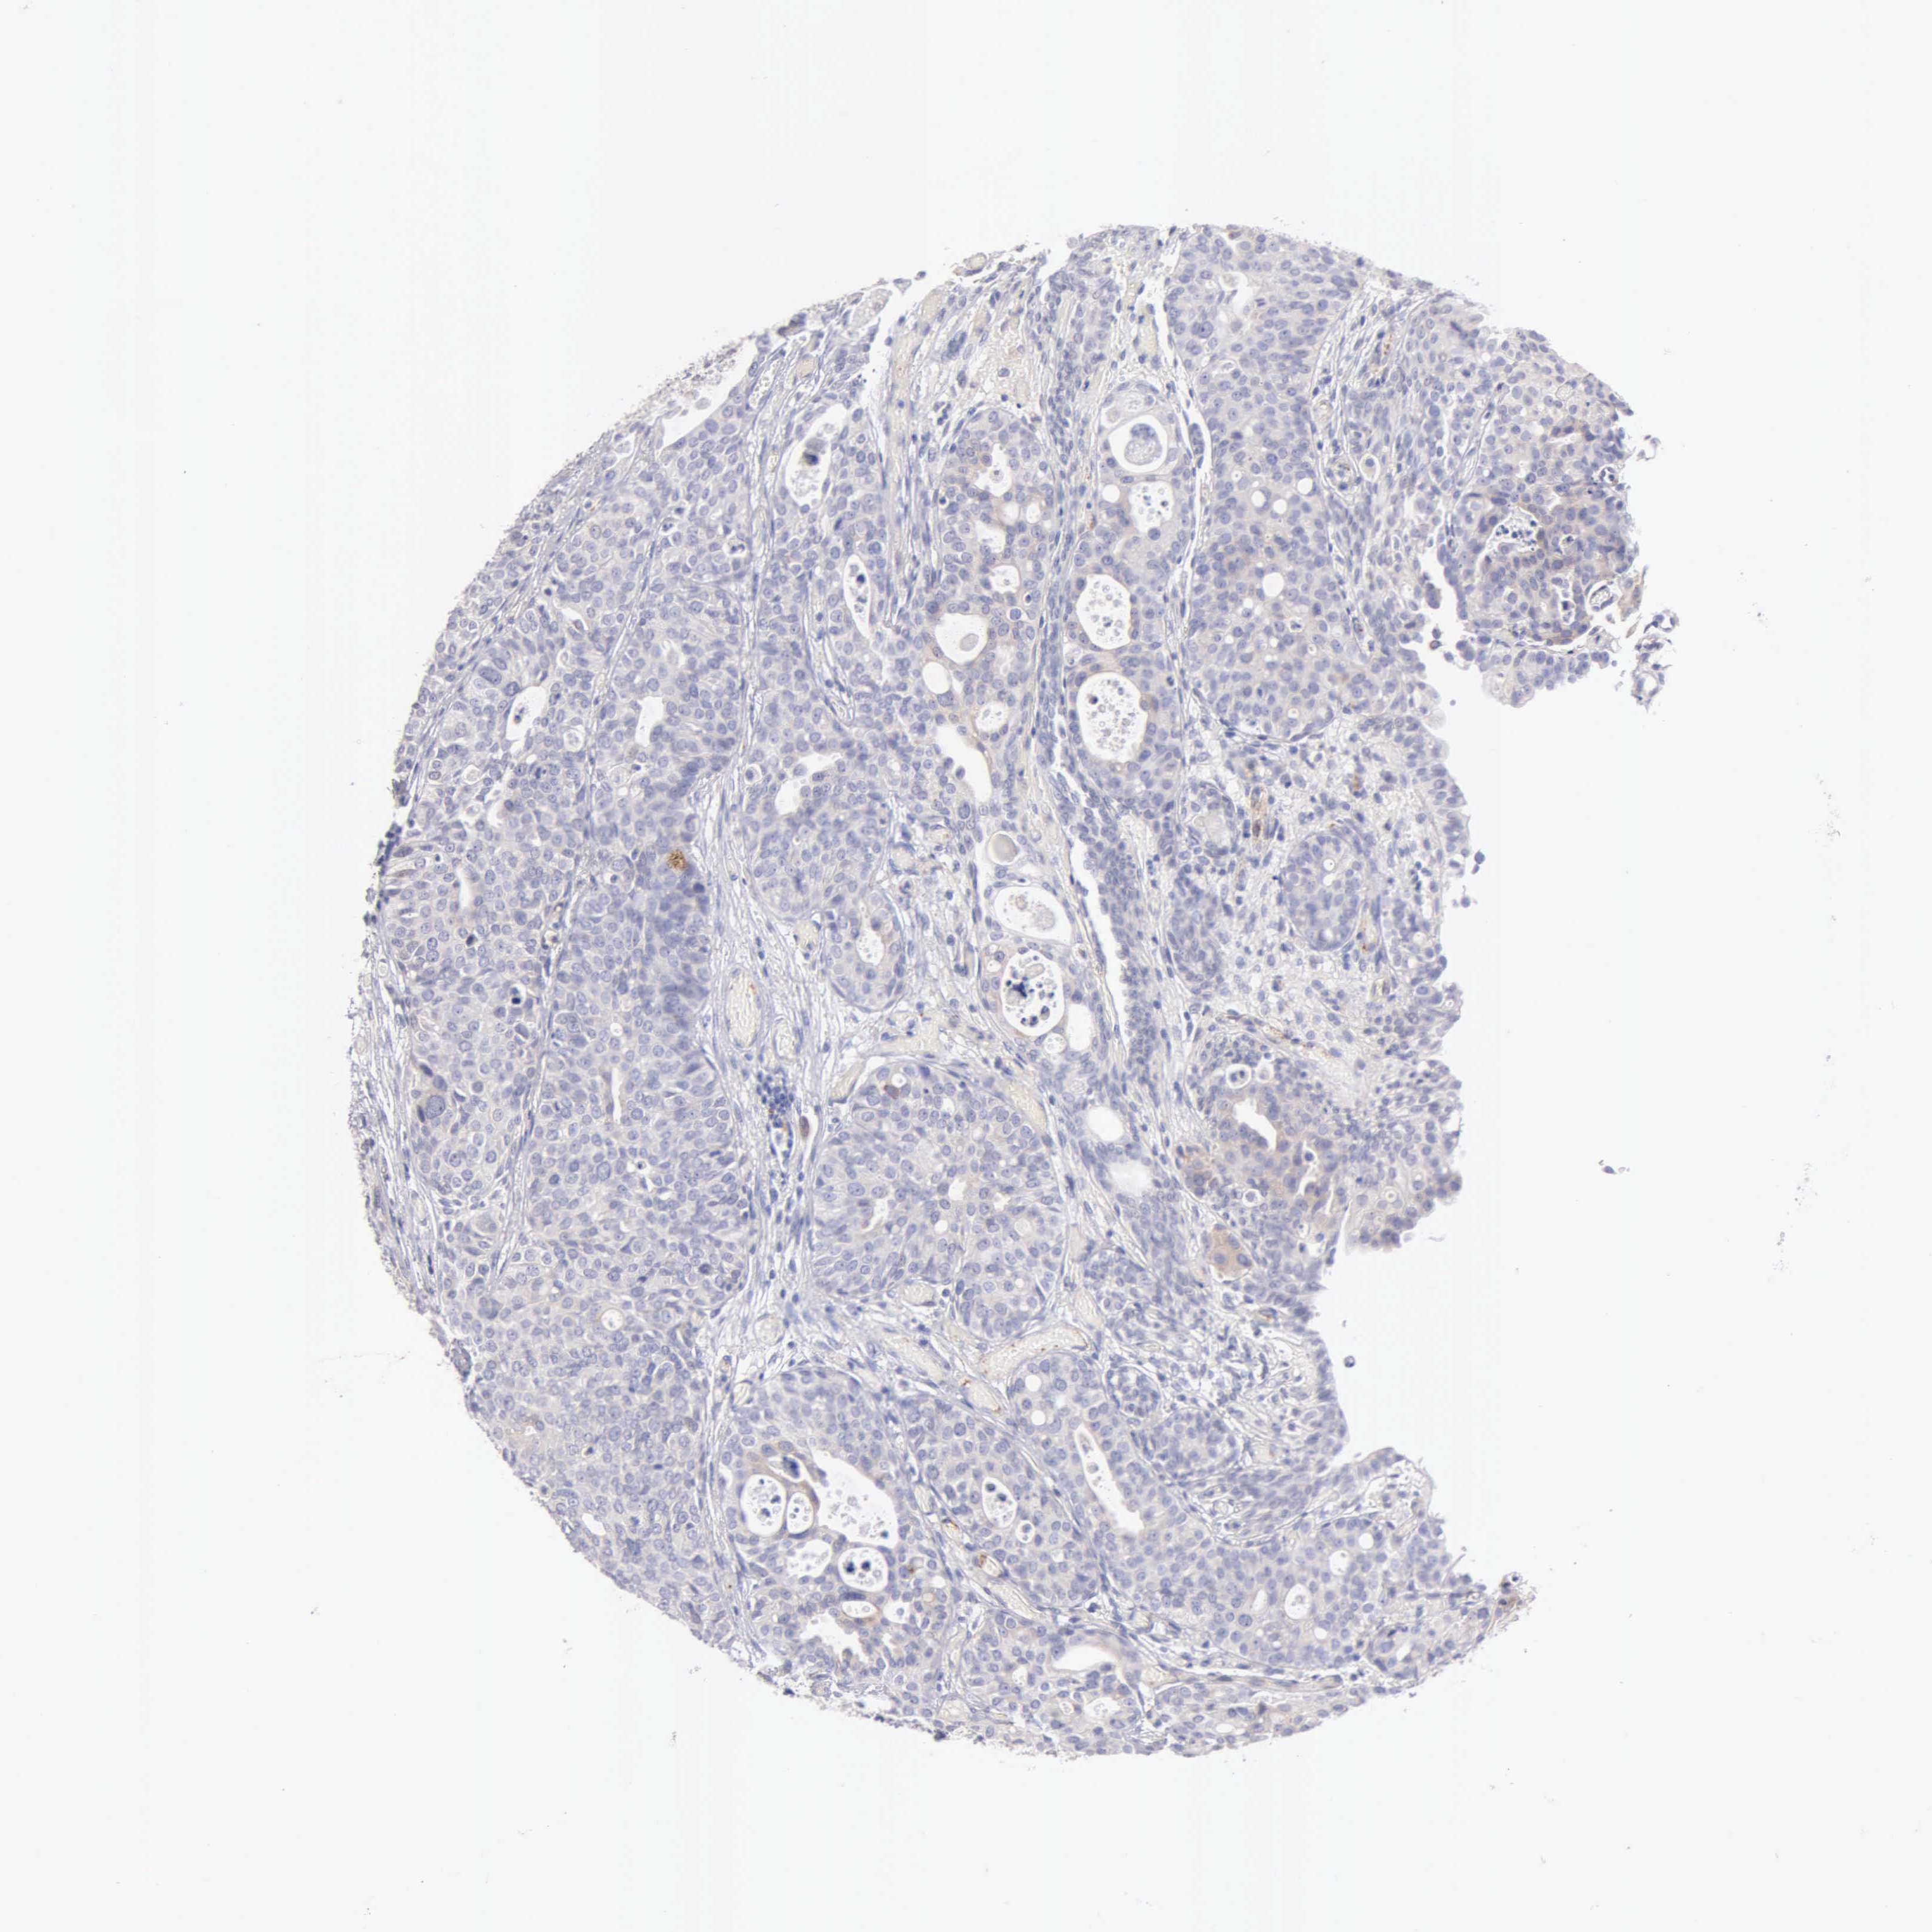

UROTHELIAL CANCER - Protein expressioni

A mouse-over function shows sample information and annotation data. Click on an image to view it in a full screen mode. Samples can be filtered based on level of antibody staining by selecting one or several of the following categories: high, medium, low and not detected. The assay and annotation is described here.

Antibody stainingi

Antibody staining in the annotated cell types in the current human tissue is reported as not detected, low, medium, or high, based on conventional immunohistochemistry profiling in selected tissues. This score is based on the combination of the staining intensity and fraction of stained cells.

Each image is clickable and will lead to virtual microscopy that enables deeper exploration of all samples and also displays staining intensity scores, fraction scores and subcellular localization as well as patient and tissue information for each sample.

Antibody HPA001462

Antibody CAB000157

Urothelial carcinoma, High grade

Urothelial carcinoma, Low grade

Adenocarcinoma, NOS